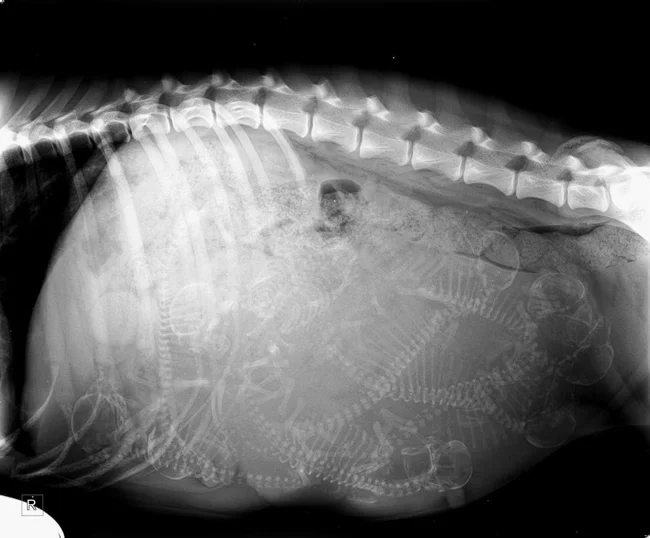

Снимок беременной собаки